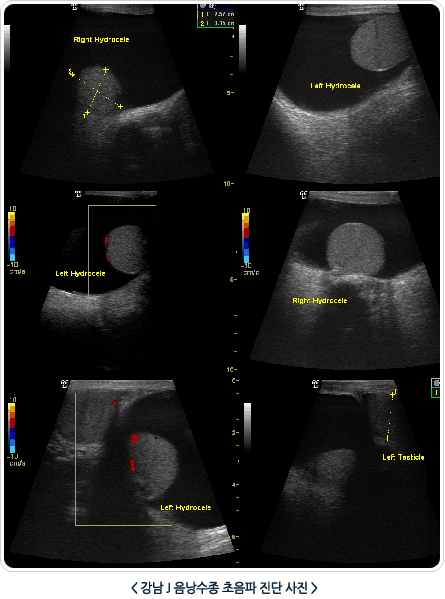

2. Ä÷¯ µµÇ÷¯ ÃÊÀ½ÆÄ °Ë»ç

À½³¶¼öÁ¾À» °¡Àå Á¤È®ÇÏ°Ô Áø´ÜÇÏ´Â ¹æ¹ýÀ¸·Î À½³¶¼öÁ¾ÀÇ ¼ºÁú, °íȯ¾ÏÀÇ À¯¹«, °íȯ ¶Ç´Â ºÎ°íȯÀÇ ÀÌ»ó À¯¹«¸¦ µ¿½Ã¿¡ È®ÀÎ ÇÒ ¼ö ÀÖ´Â Áø´Ü¹æ¹ýÀÔ´Ï´Ù.? Ä÷¯ µµÇ÷¯ ÃÊÀ½ÆÄ °Ë»ç¿Í Ç÷¾×°Ë»ç¸¦ µ¿½Ã¿¡ ½ÃÇàÇØ¼­ °íȯÁ¾¾ç¿¡ ´ëÇÑ Áø´Üµµ º´ÇàÀ» ÇÒ ¼ö ÀÖ½À´Ï´Ù.